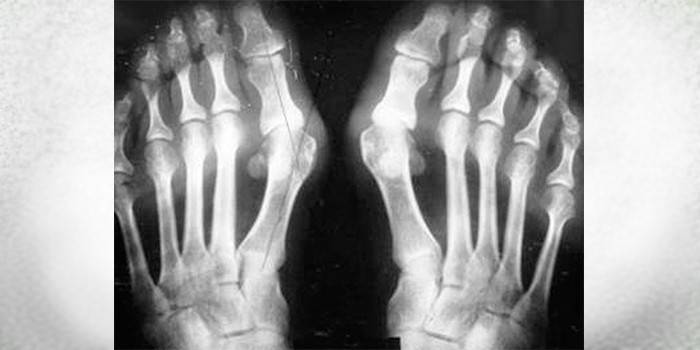

Aby prawidłowo przepisać leczenie, scharakteryzować objawy choroby, porównać patologię z wcześniej badanymi, przyjęto klasyfikację koślawego palucha płaskiego. Nasilenie procesu odróżnia stadia choroby, w zależności od kąta przesunięcia palca w stopniach:

- pierwsze - mniej niż 20 - ból i dyskomfort są nieobecne;

- drugi - do 30 - występuje niewielki dyskomfort;

- trzeci - do 50 - jest stały ból;

- czwarty - ponad 50 - dyskomfort podczas chodzenia, pojawienie się odcisków, zwiększone objawy.

Ważną częścią środków diagnostycznych są badania sprzętu. Przypisane:

- radiografia stóp - ujawnia szczegóły zmian w tkance kostnej, obniżenie wysokości łuku;